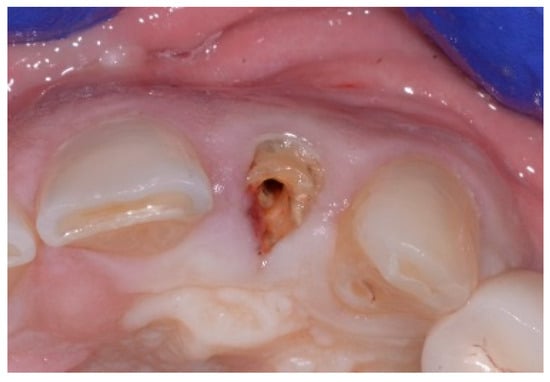

A 43-year-old female patient in good health and a non-smoker presented with a history of endodontic failure of the maxillary central incisors. She was interested in the replacement of her teeth with endosseous implants. The teeth had previously been treated endodontically with no lesion regression. Endodontic surgery had also failed. Clinical examination revealed class 1 mobility and a scar on the soft tissue above the maxillary anterior teeth. Radiographic examinations revealed the presence of chronic periapical lesions associated with teeth number 8 and 9, and clinically there was minimal remaining tooth structure (Figure 1). A treatment plan involving the placement of two immediate implants followed by future ceramic crowns was presented and accepted by the patient.

Figure 1.

Clinical view of existing maxillary incisors.